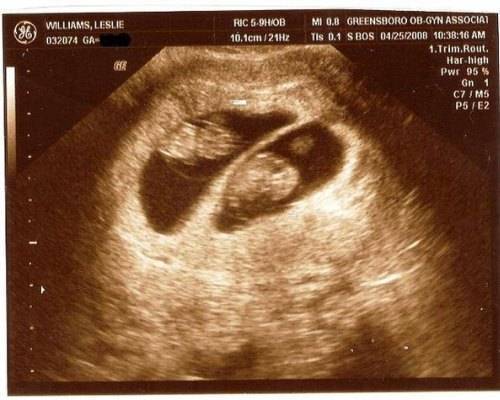

Увидеть двойняшек на мониторе при ультразвуке можно начиная с самых ранних сроков. В это время малыши только-только начинают оформляться, и на экране видно просто 2 темных пятнышка. Но у каждого из них уже есть маленькое сердечко, которое вполне реально услышать.

Если будущая мама впервые узнала о двойняшках на первом плановом ультразвуке в 9-11 недель, она может увидеть полноценных эмбрионов длиной в 4,5-4,8 см. Малыши в это время уже двигаются, у них сформированы внутренние органы, появились пальчики. К 14-й неделе плоды уже достигают в длину 12 см – в это время мамин животик начинает активно расти. В 12 недель длина каждого из близнецов – около 6 см, вес – приблизительно 8 гр.

К 16-17-й неделе – время второго скрининга – будущие детки уже весят по 100 гр, у них появляется слух. На 20-й неделе необходимо второе плановое сканирование. На этом этапе беременности близнецы уже весят по 350 гр, иногда видно, что один из малышей бывает чуть крупнее другого. Ничего опасного в этом нет – после рождения дети быстро выровняются в весе.

При проведении ультразвукового исследования на качественном современном оборудовании высококвалифицированным специалистом многоплодная беременность может быть диагностирована уже на 5-й неделе. На мониторе будет видно 2 и более эхонегативных образования, если развиваются разнояйцевые близнецы.

При беременности однояйцевыми близнецами диагностика затруднена. Выявить такую беременность можно примерно на 7–8 неделе, когда зародыши хорошо визуализируются. Однако и в этом случае возможна ошибка.

В ходе исследования сонолог определяет размеры матки, плодного яйца и эмбриона, количество эмбрионов (или плодов, если исследование проводится после 8-й недели беременности), их расположение в матке и место локализации хориона или плаценты (после 12-й недели). Также оценивается развитие малышей, наличие или отсутствие у них патологий или маркеров хромосомных аномалий.